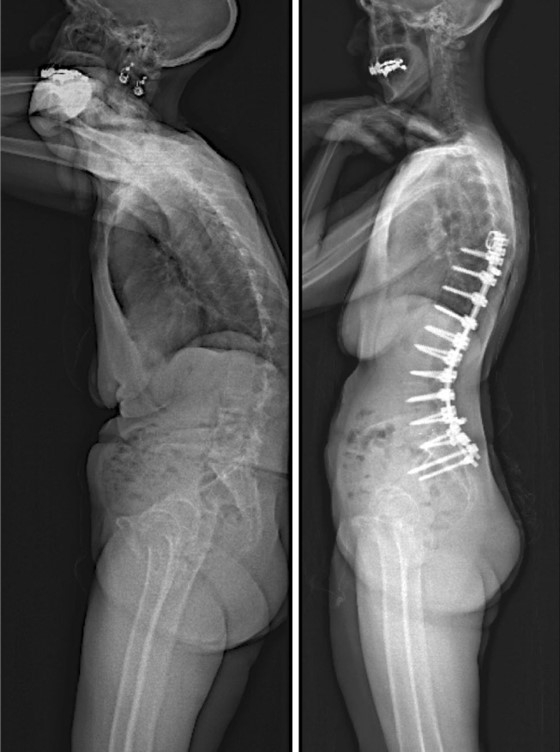

图7 术前-术后1个月-术后1个月外观